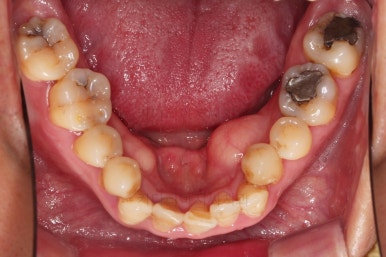

1. 초진 시 입안의 모습

부산구순구개열교정 키다리아저씨치과에 처음 내원하셨을 당시의 입안의 모습입니다.

구순구개열 환자분의 일반적인 입 안의 특징은 다음과 같습니다.

골 결손부위의 치아 결손이 빈번하다.

구개열 봉합술을 어린 나아이에 받기 때문에, 해당 부위의 상흔이 남는다.

상흔의 영향으로(피부 상처도 일반 피부 보다는 상처가 아문 부위가 더 단단하죠.) 입천장의 잇몸이 굉장히 단단하다.

그래서 가로폭의 성장이 잘 되지 못하여 악궁(치아가 배열된 U자 형태)이 협착된 경우가 많다.

공간 부족으로 치열이 매우 삐뚠 경우가 많다.

공간 부족과 악궁 형태 등으로 인해 부정교합이 함께 나타난다.

골 결손부위 근처의 치아는 뼈가 약한 경우가 많아 튼튼하지 못하고 만지면 흔들리는 경우가 많다.

이번 환자분도 이와 같은 일반적인 특징이 그대로 나타나 있었습니다.

양측성 구순구개열이었으므로 작은 앞니(대문니와 송곳니 사이)가 양쪽 다 결손이었고, 또 다른 이유로 아래 앞니도 1개 없는 상태였습니다.